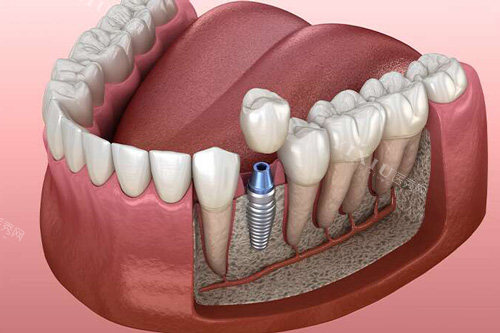

一、种植牙价格

种植牙是修复缺失牙齿的一种有效方法,不同品牌的植体价格差异较大。

国产柯润玺种植牙:2580元/颗

韩国进口种植牙:3380元/颗

韩国登腾种植牙:4000元起/颗(博恩口腔6280元起/颗)

国产百康特种植牙:6500元起/颗

德国费亚丹植体:12000元起/颗

意大利西傲CLC种植牙:8800元起/颗

法国安卓健种植牙:9800元起/颗

国产康盛种植体:5100元起/颗

前门牙种植牙:4987元起/颗

牙周炎种植牙:8455元起/颗